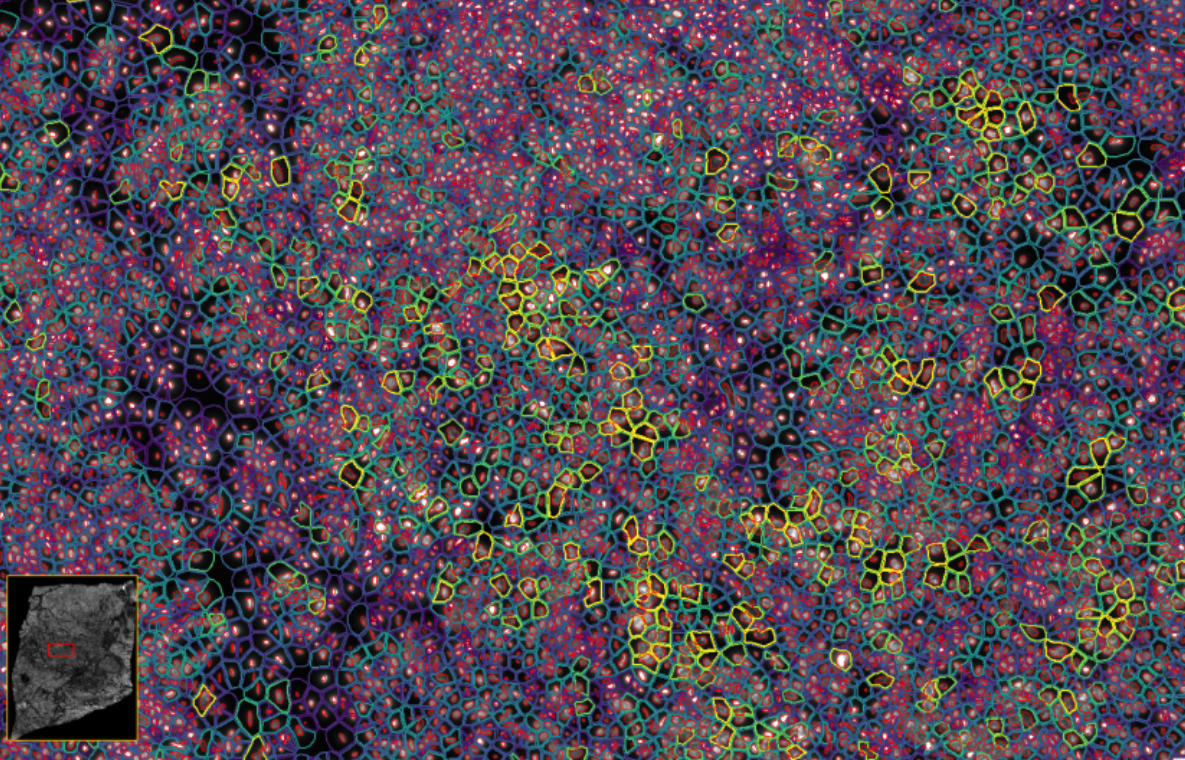

ͼ4-1£ºÊ¹ÓÃDAPI¶Ôϸ°ûºËȾɫ£¬£¬£¬£¬£¬£¬£¬ÍŽáÉî¶ÈѧϰҪÁìÍÆ¶ÏÍêÕûµÄϸ°û½çÏß

ͼ4-2£ºÊ¹ÓÃDAPI¶Ôϸ°ûºËȾɫ£¬£¬£¬£¬£¬£¬£¬ÍŽáÉî¶ÈѧϰҪÁìÍÆ¶ÏÍêÕûµÄϸ°û½çÏß